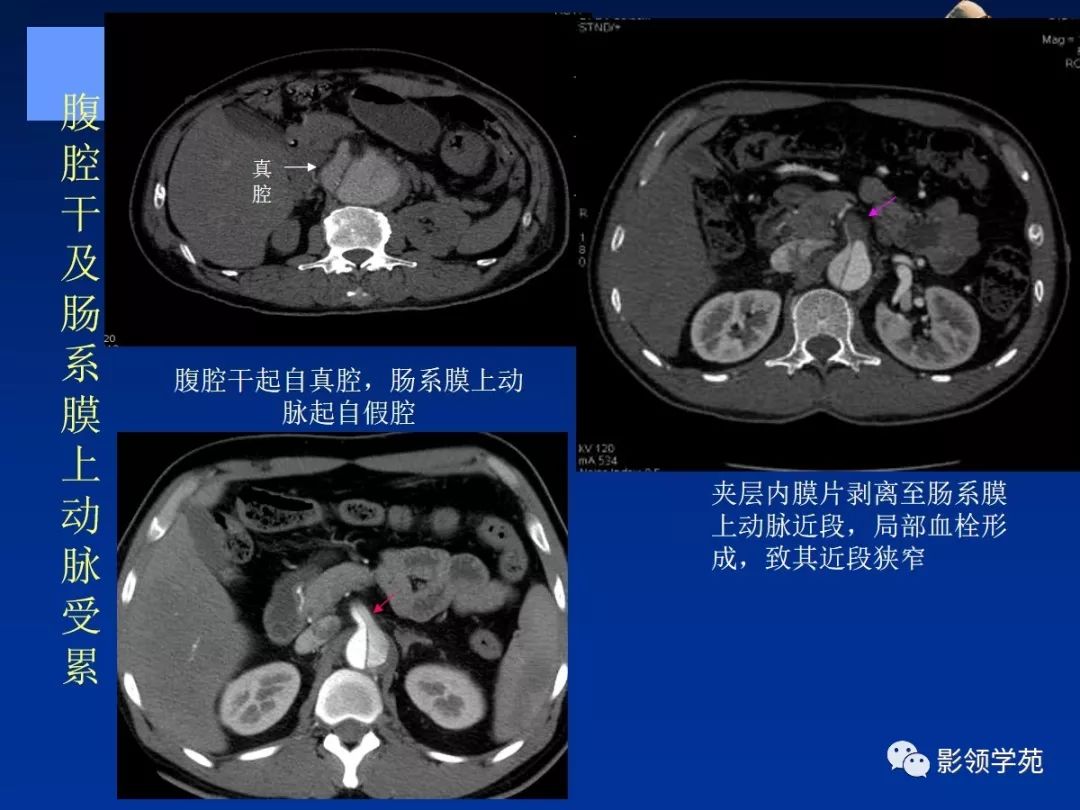

典型AD:

病理学特点:

- 内膜撕裂

- 真假“双腔” ,存在交通

- 远段同时存在再破口